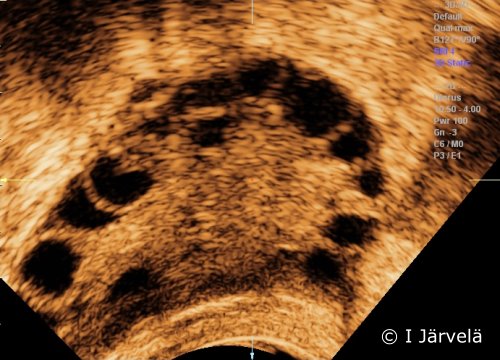

Antral follicles (ultrasound scan). Antral follicles (ultrasound scan)

Picture: Ilkka Järvelä; text: Dimitrios Scordas